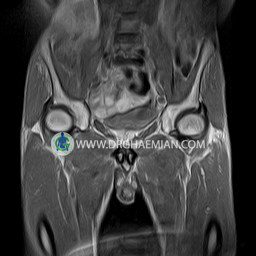

پزشکان اغلب از تصویربرداری ام آر آی برای تشخیص و درمان عارضه های پزشکی که فقط با استفاده از اشعه ایکس یا میدان مغناطیسی و امواج رادیویی قابل مشاهده است، استفاده می کنند. دستگاه ام آر آی تصاویر دقیق از ساختار های داخلی بدن ایجاد می کند. در این کیس استئومیلیت لگن، آتروز و سنیویت دیده می شود.

HIP JOINT MRI

( without contrast )

Technique : coronal STIR , coronal T2 , Axial T1 , axial T2 .

The femoral heads and acetabula are normal shape , signal intensity and the femoral heads are well covered by the acetabular margins .

The joint spaces are of normal width without fluid collection .

The articular surfaces are smooth and congruent and show normal cortical thickness .

– Heterogeneous signal change (high T2/STIR , low T1) in proximal metaepiphysis of left femur without articular surface irregularity suggestive for bone bruise (stress fracture?), osteomyelitis & arthritis and marrow infiltration (less probable)

– Left hip joint effusion suggestive for synovitis

are seen.

COMMENT: Clinical correlation and MRI with contrast are recommended.